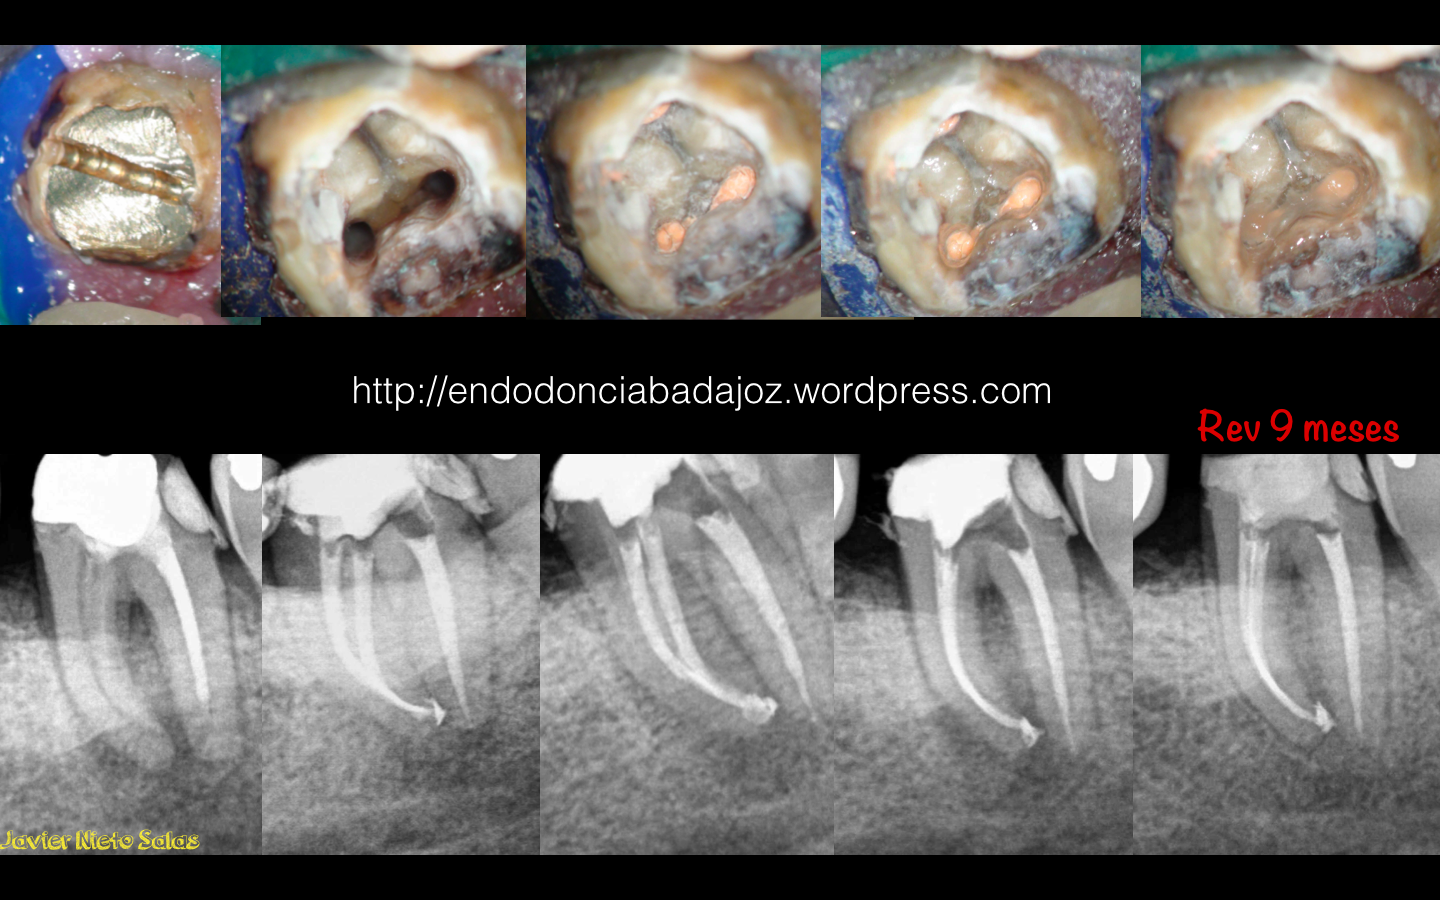

Como veremos en estos dos casos que subimos hoy, si realizamos un tratamiento correcto, que nadie dice que sea sencillo, obtendremos , en la generalidad de los casos, un MUY BUEN PRONÓSTICO.

1) Caso A: Motivo de fracaso, subobturación de los conductos mesiales. Vemos como corrigiendo el problema, es un tratamiento predecible

2) Caso B: Conductos omitidos y subobturación del conducto distal. Vemos la regeneración de la lesión a los 9 meses.

Con lo que concluyo con la frase que dije al principio:

EL TRATAMIENTO DE ENDODONCIA ES UN TRATAMIENTO MUY PREDECIBLE CON ALTAS TASAS DE ÉXITO. ( no de supervivencia, que también)